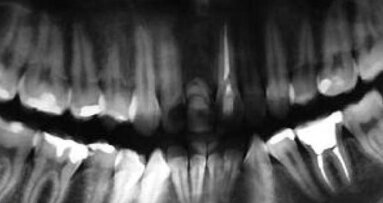

Badanie kliniczne i radiologiczne wykazało niewielkie poziome zaniki kostne w obszarze szczęki i żuchwy, ogólna higiena obszaru jamy ustnej została oceniona jako dobra. Nie zaobserwowano ruchomości zębów, a kieszonki dziąsłowe nie zostały sklasyfikowane jako patologiczne.

Po upływie 22 miesięcy od wykonania finalnej rekonstrukcji protetycznej doszło do poprzecznego pęknięcia korzenia zęba #12. Podjęto decyzję o natychmiastowej implantacji w tym miejscu. Wybrano poddziąsłowy protokół gojenia. Pacjentka nie wyraziła zgody na wykonanie przeszczepu łącznotkankowego celem zwiększenia objętości dziąsła związanego w okolicy przyszyjkowej implantu.

Odsłonięcia struktur kostnych dokonano poprzez wykonanie nacięcia poprowadzonego podniebiennie od szczytu wyrostka bez wykonywania horyzontalnych cięć odbarczających. Wprowadzony został implant Astra 3,5 mm (AstraTech AB, Szwecja), a powstała od strony przedsionkowej dehiscencja i fenestracja została pokryta materiałem BioOss (Geistlich Pharma, Szwajcaria) oraz membraną resorbowalną BioGide. Rana została zaszyta szwami pojedynczymi.